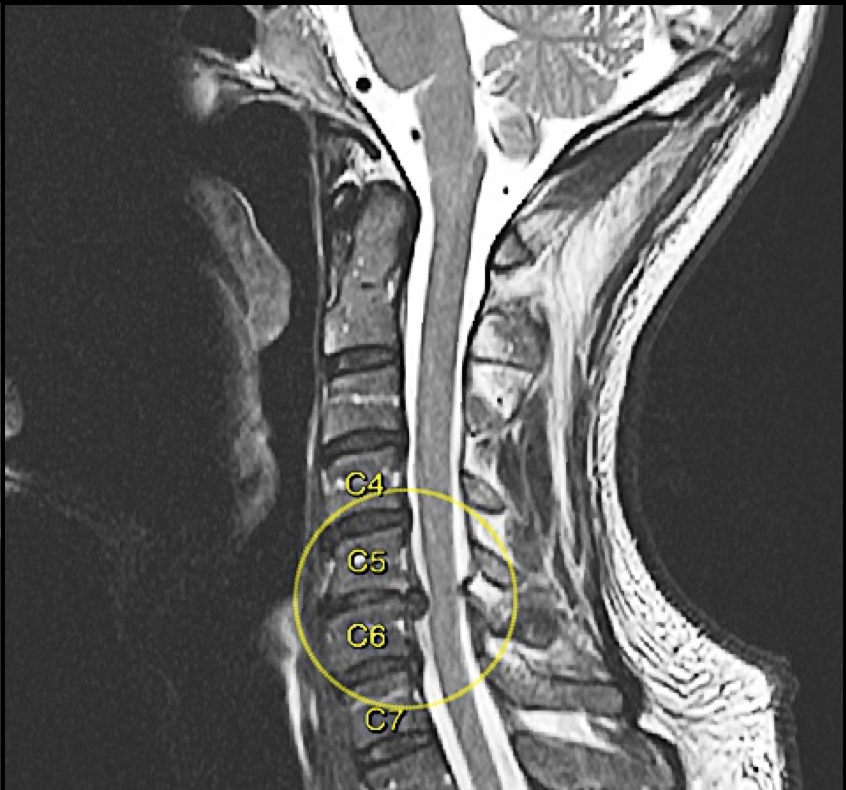

Paciente: APR

Edad: 55 años

Diagnóstico: Extrusión Discal C5-C6 Posterocentral, con compresión del cordón medular.

Tipo de Cirugía: Discoidectomía Cervical anterior C5-C6, más fusión segmentaria, con caja de PEEK.

Fecha de la cirugía: Marzo 26 del 2018